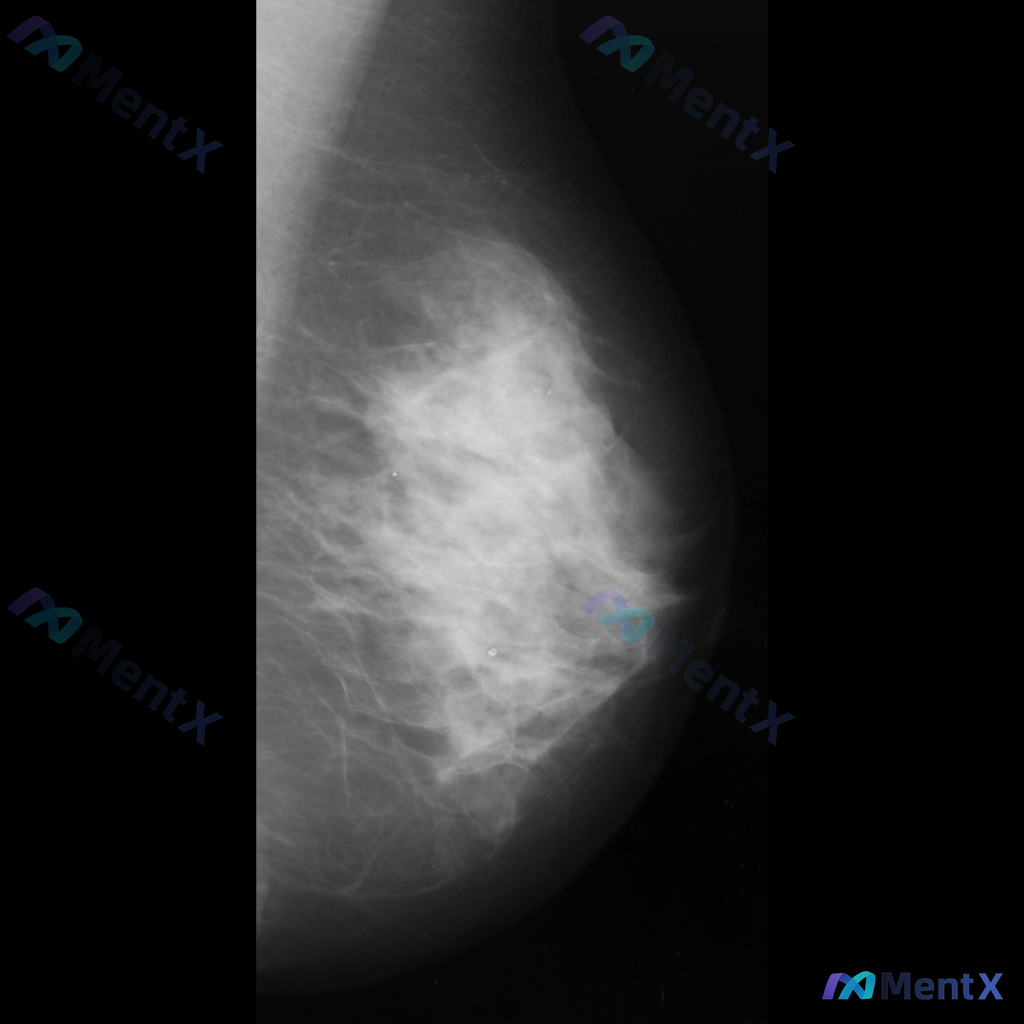

整理到一张乳腺钼靶影像的读片资料,分享给大家讨论。 影像表现:左乳中上象限可见一不规则形高密度致密影,边界部分模糊;内部可见细小、簇状分布的钙化影;同时局部乳腺腺体结构有轻度扭曲和牵拉。 目前需要判断的是,这组表现更支持哪一类情况?

整理到一份乳腺影像的分析资料,想请大家一起讨论看看。 基本信息: - 影像类型:左侧乳腺钼靶内外斜位(MLO) 影像主要表现: 1. 左侧乳腺中上部及外侧可见局灶性结构扭曲 2. 乳腺腺体组织以纤维腺体为主,密度较高,为不均匀致密型(ACR BI-RADS C型) 3. 腺体可见多发斑片状、结节状高...

整理到一张乳腺钼靶影像资料,影像所见:左乳中上象限可见不规则高密度致密影,边界部分模糊或伴毛刺状改变,局部乳腺组织结构可见轻度扭曲。 想和大家讨论一下:单看这张影像的异常表现,你认为用哪个术语描述最贴切?